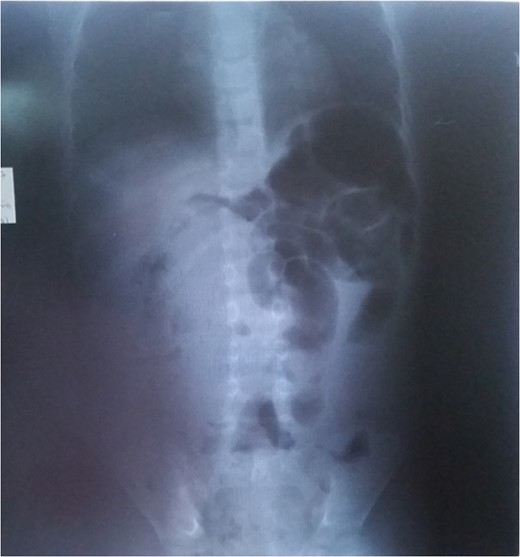

The gold standard imaging modality for mesenteric lipomas could be computed tomography scans and or magnetic resonance imaging but as a result of the limited availability of such an equipment in our setting, ultrasonography was used [3]. Mesenteric lipoma ultrasonography shows a homogenous well-encapsulated mass which echogenic (Fig. 3) [9].